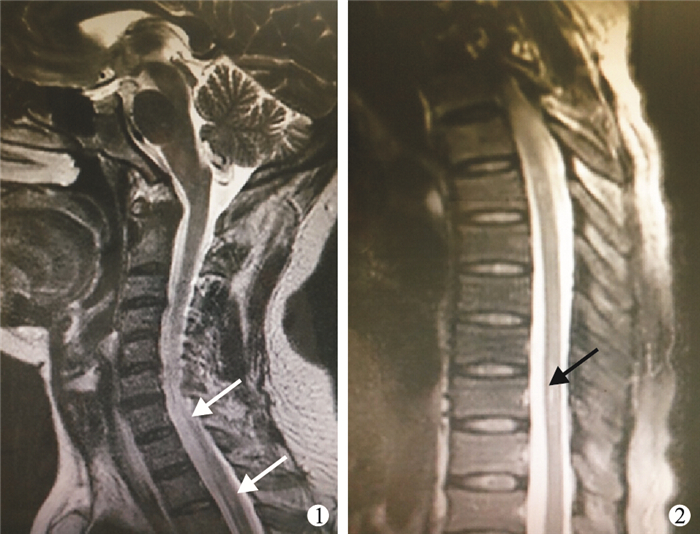

患者????女,50歲。因“雙下肢及軀干感覺異常2+個月,肢體肌肉抽搐21 d”于2013年2月18日入住我院。病史:患者于2012年12月出現雙足麻木,遂向上發展至雙側肋緣以下,伴雙下肢僵硬感,于當地醫院就醫,胸腰椎MRI平掃:脊髓胸段中央管周圍多處小斑片狀異常信號影。免疫檢查:抗核抗體1︰320,抗SSA抗體陽性(+++),抗SSB抗體陽性(+),抗Ro52陽性(+++)。唾液腺顯像:唾液腺攝取功能重度下降。下唇腺活體組織檢查(活檢):淋巴細胞灶>1。給予激素及其他藥物治療,癥狀無緩解,出院口服潑尼松25 mg/d,期間口服卡馬西平后出現雙唇、會陰部皮膚紅腫,遂停用。2013年1月11日就診于我院神經內科,頭顱及頸椎增強MRI:頭顱未見明顯異常,頸2~6脊髓異常信號影(圖 1),為脊髓炎可能。胸椎增強MRI:胸段脊髓內帶狀長T1、長T2信號影(圖 2),多為脊髓炎。腦脊液:細胞數不高,微量蛋白0.57 g/L,糖、氯正常,IgG合成率22.9 mg/d(正常上限5.81 mg/d),涂片、培養均陰性。免疫:IgG 18 g/L,抗核抗體1︰320,抗SSA抗體+++,抗SSB抗體可疑陽性,補體、類風濕因子、抗中性粒細胞胞漿抗體、抗心磷脂抗體均陰性。診斷“①干燥綜合征;②脊髓炎;③藥疹”,給予注射用甲潑尼龍琥珀酸鈉(商品名:甲強龍)1 000 mg/d靜脈滴注5 d,后減為醋酸潑尼松片(商品名:強的松)60 mg/d口服,環磷酰胺0.8 g靜脈滴注1次,癥狀好轉出院。出院后3 d(2013年1月29日)出現陣發下肢燒灼感,每次間隔10余分鐘發作,每次持續數秒自行緩解,發作同時出現對側肢體肌肉抽搐,以右側肢體為重,伴上肢麻木,無大小便障礙,自行停用我院藥物,再次就診于當地醫院,行腦脊液檢查未見異常,予注射用甲潑尼龍琥珀酸鈉1 000 mg/d靜脈滴注3 d,后減為80 mg/d,環磷酰胺0.8 g靜脈滴注1次,無明顯緩解。于2013年2月18日入我科住院治療。既往史:口眼干10余年,數年前開始多顆牙齒逐漸變黑。入院體格檢查:體溫、血壓不高,神清,雙瞳等大等圓,光反射靈敏,伸舌居中,舌面干,口內見多顆齲齒,雙下肢輕度水腫。四肢肌力、肌張力正常,雙側膝踝反射未正常引出,右側肢體及右側軀干胸4以下平面痛溫覺減退,雙側髕陣攣及踝陣攣未引出,病理征未引出。輔助檢查:眼科檢查:角膜染色+~++。肌電圖上下肢所檢神經、肌肉未見異常。胸椎增強MRI:胸段脊髓內帶狀長T1、長T2信號影,多為脊髓炎,與2013年1月胸椎增強MRI相比,部分病變較前減輕。免疫固定電泳未見單克隆條帶。治療:給予注射用甲潑尼龍琥珀酸鈉120 mg/d,靜脈滴注9 d,減為口服醋酸潑尼松片60 mg/d,肢體麻木僵硬減輕,陣發肢體強直抽動消失出院。于2013年3月6日出院。此后患者每個月前來我科行環磷酰胺1 g沖擊治療,共計6次,最后1次為2013年8月,患者訴偶有肢體麻木,未再出現肌肉抽搐。